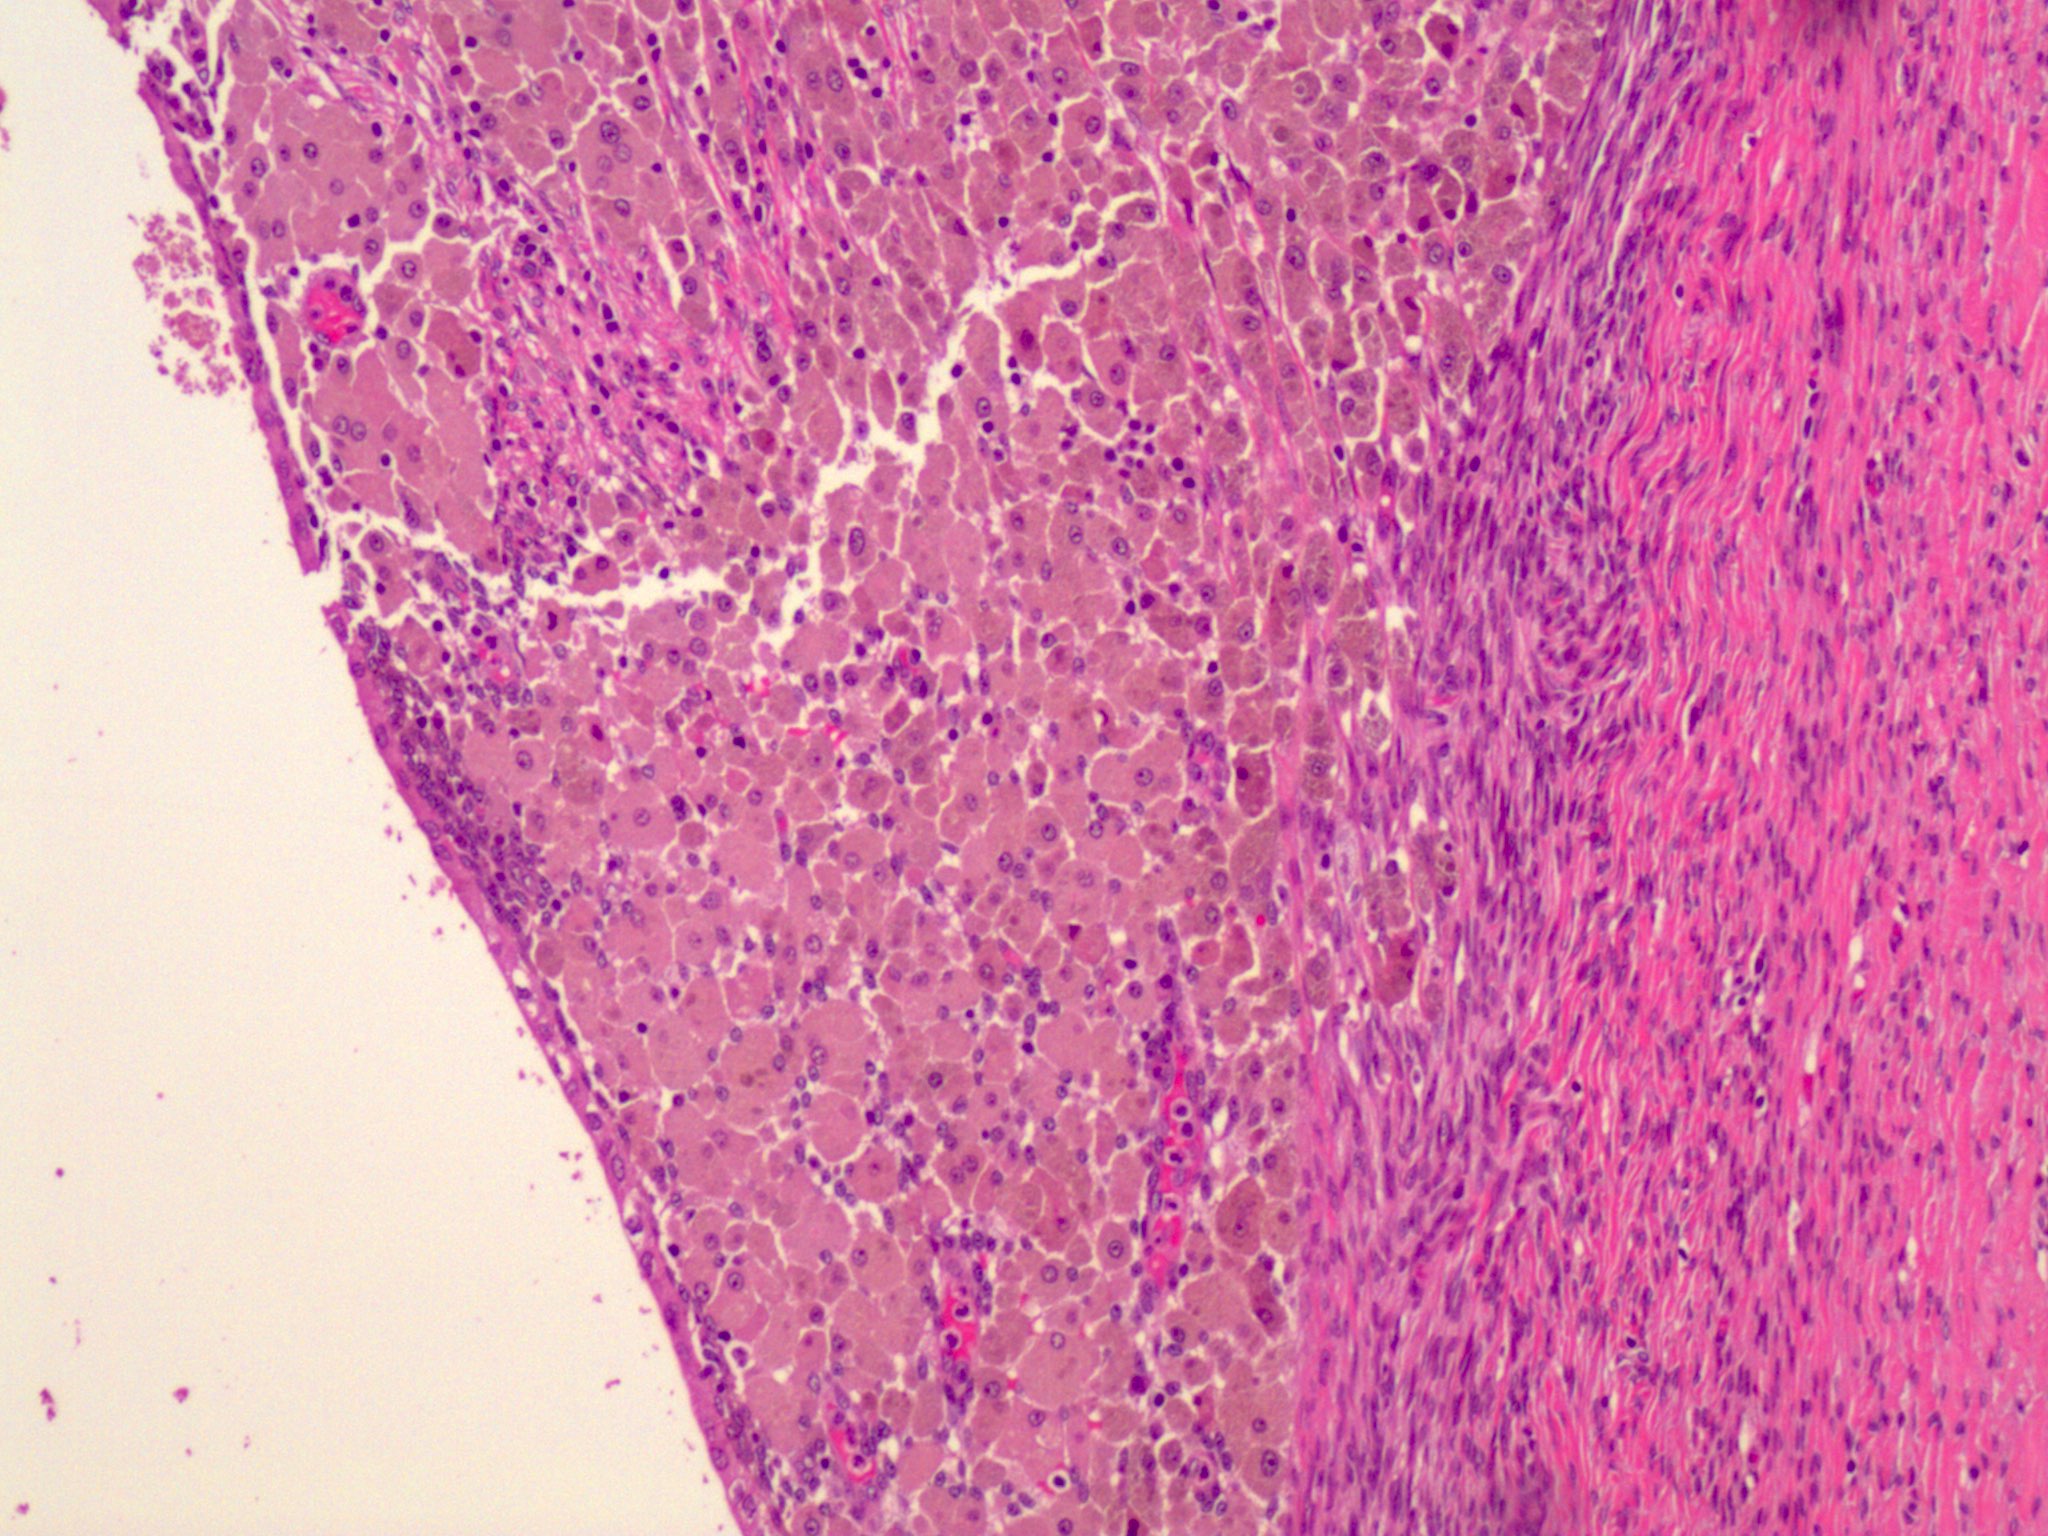

Microscopic (histologic) images

Microscopic (histologic) description

- Endometrial type glands

- Müllerian type epithelium (can be atrophic to cycling endometrium)

- Can show degenerative atypia (enlarged smudgy nuclei) or metaplasia

- Endometrial type stroma

- Often contains fine capillary network

- Endometriotic cyst / endometrioma: cystic form of endometriosis

- Ovarian endometriotic cysts (endometriomas) have fibrotic walls, a smooth lining and dark brown cyst contents (chocolate cyst), often adherent to adjacent organs